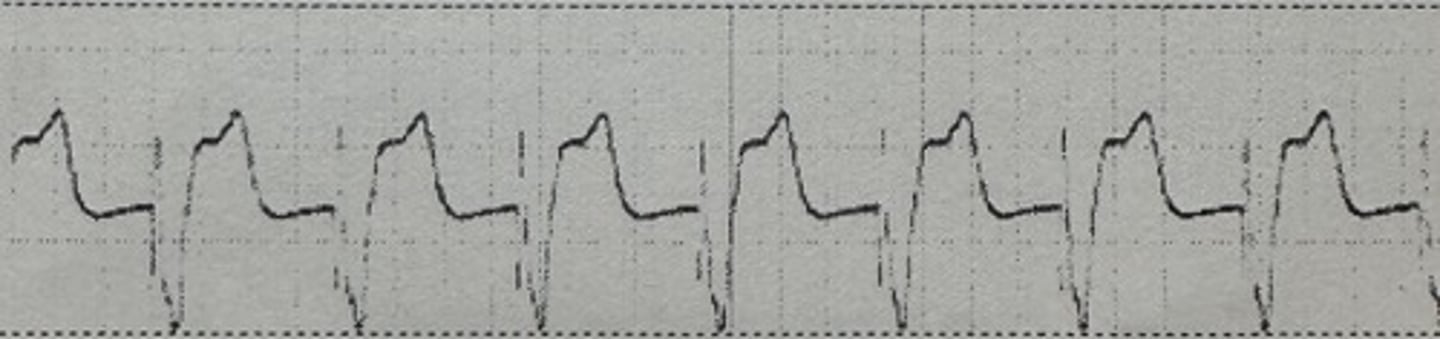

<p>identify the rhythm</p>

identify the rhythm

SR @ 90 with wide QRS ST depression and T wave inversion